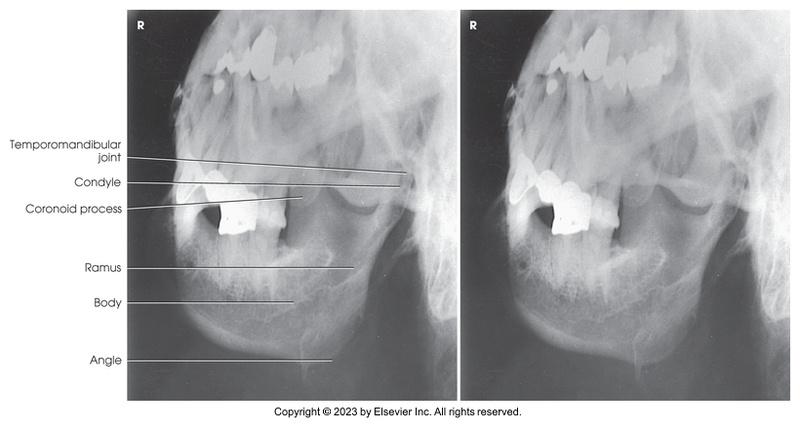

Axiolateral of mandibular rami

PA axial of the mandibular body

Axiolateral oblique of the mandibular body

Axiolateral of TMJs - Modified Schuller Method (closed mouth)

Axiolateral of TMJs - Modified Schuller Method (open mouth)

Axiolateral of mandibular ramus

Axiolateral of temporomandibular joint - Modified Schuller method (mouth closed)

Axiolateral of temporomandibular joint - Modified Schuller method (mouth opened)